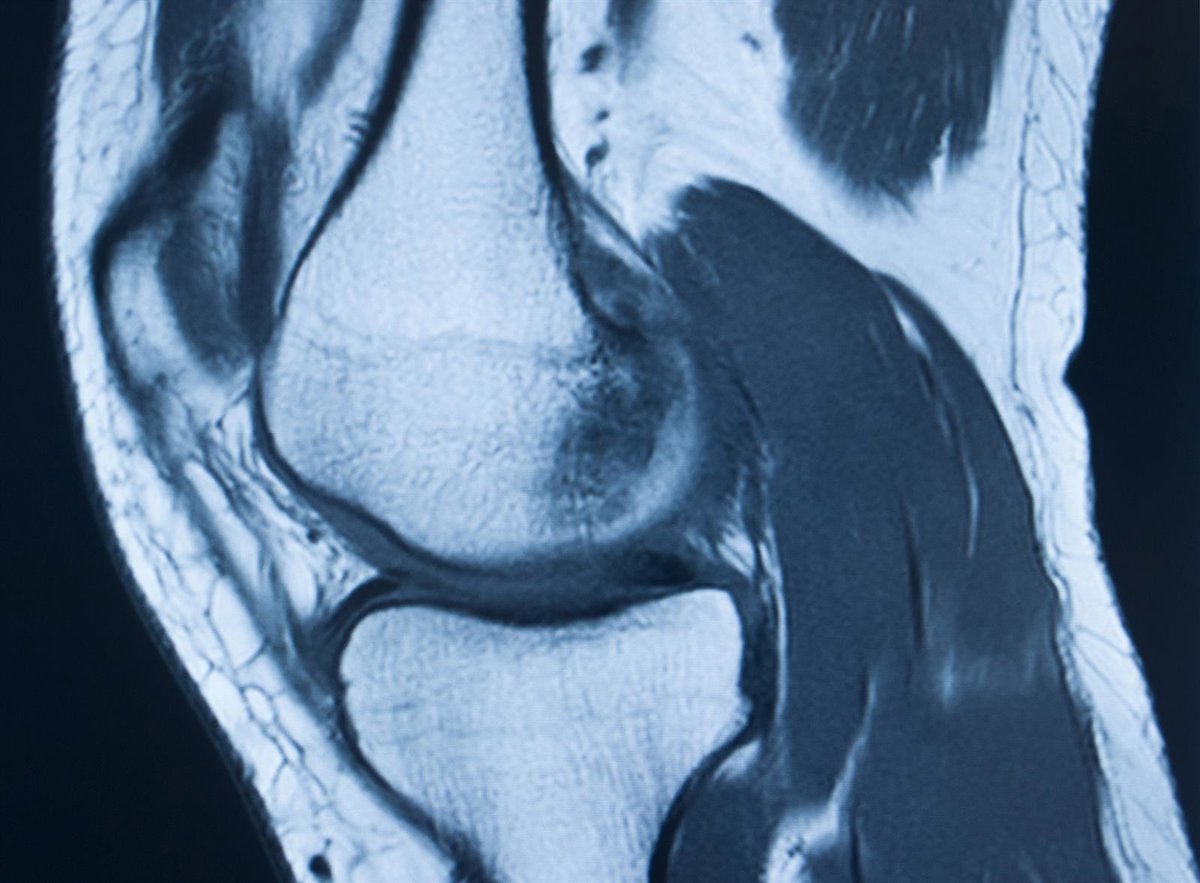

Imagen Médica De Articulación De Rodilla.

Imagen Médica De Articulación De Rodilla. - COPRIGHT PHOTOGRAPHER EDWARD OLIVE WEBSITE WWW.EDW

En concreto, IBV está investigando en el modo de realizar el análisis de las imágenes médicas, que se utilizan para diagnosticar a los pacientes. Para ello, el centro ha desarrollado metodologías de cribado o preclasificación de patologías osteoarticulares, para la detección de lesiones, mediante la utilización de técnicas de inteligencia artificial (AI).